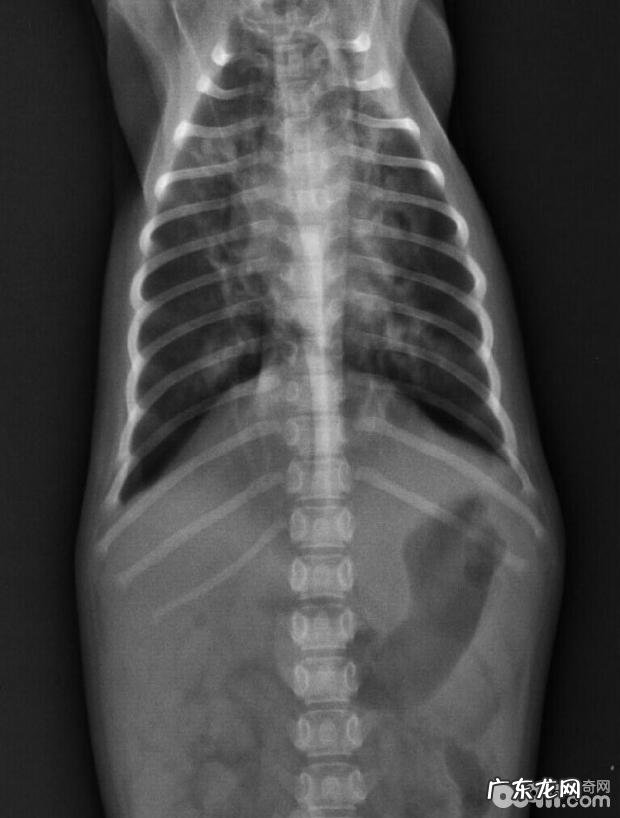

休重:9 。2kg,人体体温:40 。3℃,心跳:130/min,吸气:55/min,身型身体瘦 。精神面貌还行,鼻尖干躁,鼻腔有浓鼻涕,诱咳呈阳性,CDV(+),X光查验肺纹理增大增粗(如图所示),粪检(一切正常),血常规检查及电解质溶液基本参数见下表

X-光影象显示信息肺炎